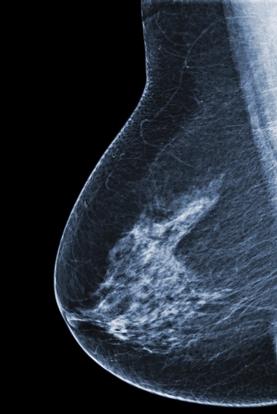

美国癌症协会发布乳腺癌排查建议书

据路透社报道,美国癌症协会建议女性在45岁时每年做一次乳腺癌排查,如过了55岁,应每两年做一次筛查。

美国医学会杂志在周二发布了该新指南。这个指南与美国联邦预防医学工作组发布的指南有很多共同点,后者是美国政府支持的专家小组,也建议50岁以上的女人每两年做一次乳腺癌筛查。

新的癌症协会指南对乳腺癌排查的好处与害处做了综合调查。调查发现,54岁以前的女性,如果每年做一次排查,比两年做一次受益更多。奥芬格尔博士说,55岁以上的女性更适合做两年一次的排查,因为这个年纪以上的女人乳房组织没那么致密了,当癌症进入终止期,其活动也就没那么活跃了。